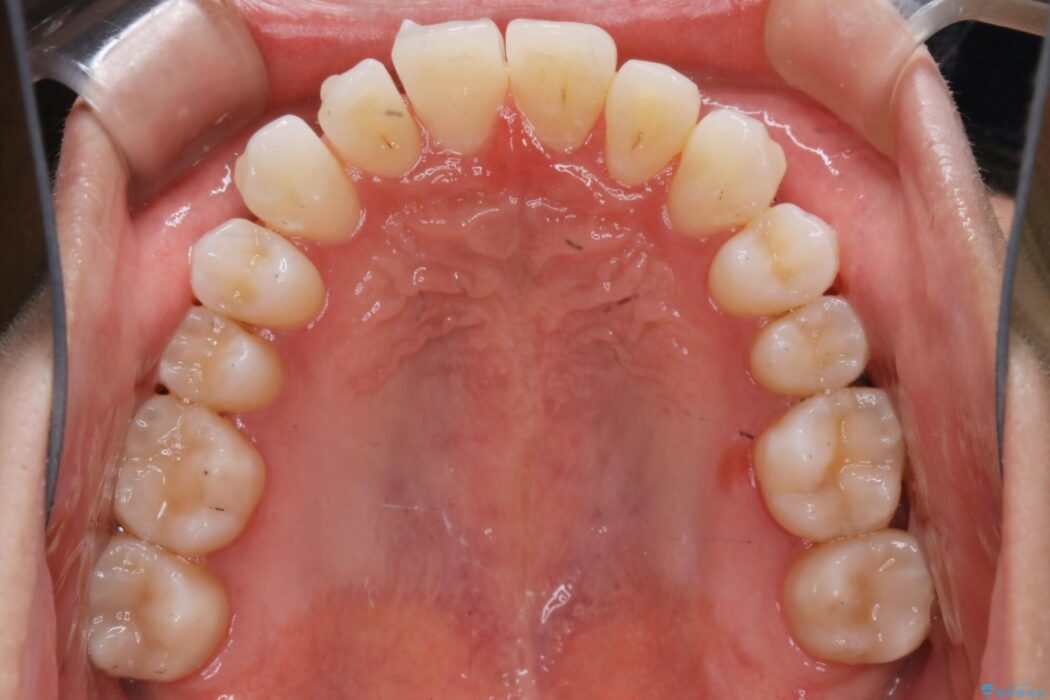

上顎歯列弓のガタガタを治療したいとのことで来院されました。

目立たない矯正装置をご希望されていたため、インビザラインでの治療をご提案しました。

前に出ていた前歯や目立つ八重歯(3番目の歯)もきれいに並び、奥歯の虫歯治療も並行して行ったため、機能面でも見た目的にも良くなり満足していただきました。

非抜歯での矯正治療ではスペースの確保が必要となります。

本症例では上記3つの方法を複合的に組み合わせた治療を行いました。